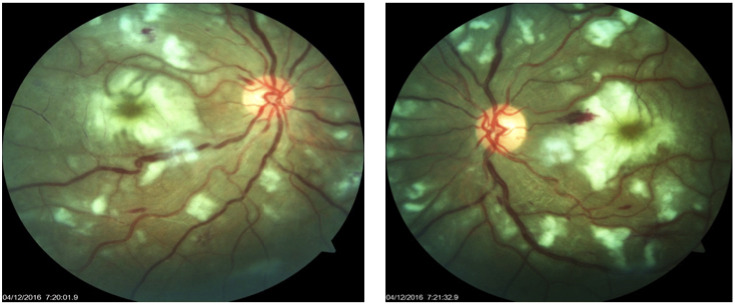

Result: A 17-year-old male presented with subacute marked diminution of vision along with arthralgia, weakness of all four limbs and development of multiple rashes around body. Fundus examination revealed bilateral multiple Purtscher flecken, pseudo-cherry red spot, and intra-retinal haemorrhages with cotton wool spots. Systemic and laboratory examinations, magnetic resonance imaging (MRI) and biopsy of tissue confirmed the diagnosis of juvenile dermatomyositis with PLR.